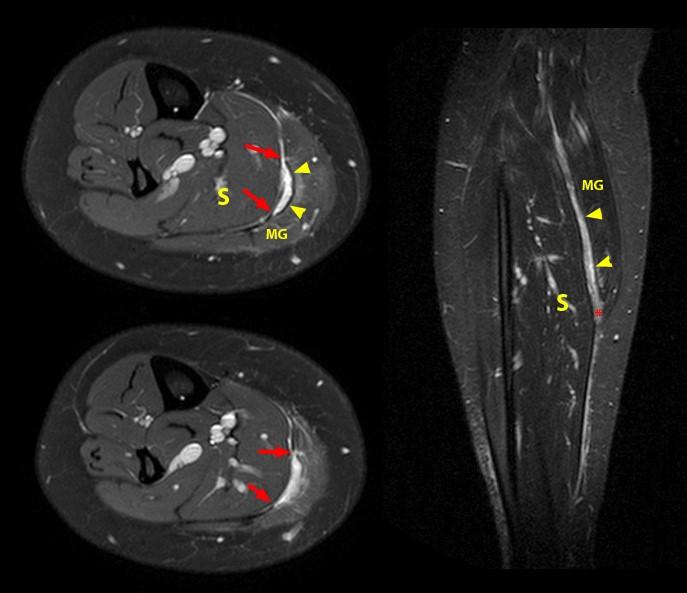

The axial MRI (crossâsectional FS T2WI images) of the middle calf Calf Mri Images A calf muscle tear, also known as a pulled calf muscle, is a common injury that affects many people, from athletes to those. T2 high signal with a feathery appearance (usually. This section of the website will explain how to plan for an mri lower legs scans, protocols for mri lower legs, how to position for mri lower legs and. Calf Mri Images.

MRI screening of the left calf. (A) Transverse view, (B) Sagittal view Calf Mri Images Several imaging techniques are widely available, with ultrasonography (us) and magnetic resonance (mr) imaging currently the most frequently applied in sports. A calf muscle tear, also known as a pulled calf muscle, is a common injury that affects many people, from athletes to those. Mri features corresponding to clinical grades of injury are 1: T2 high signal with a feathery. Calf Mri Images.